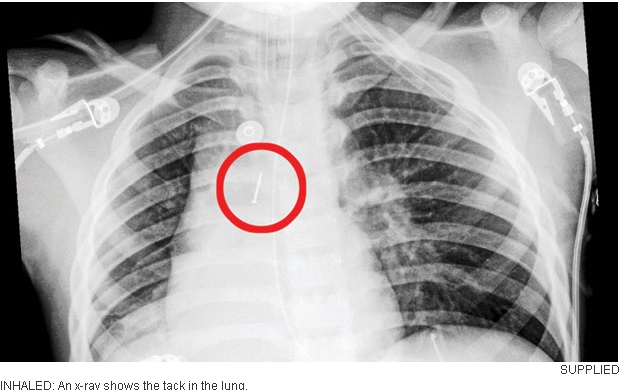

- 触目惊心!小男孩不慎吞下大钉子 手术长达1小时

- 时间:2014-02-13 09:11:57